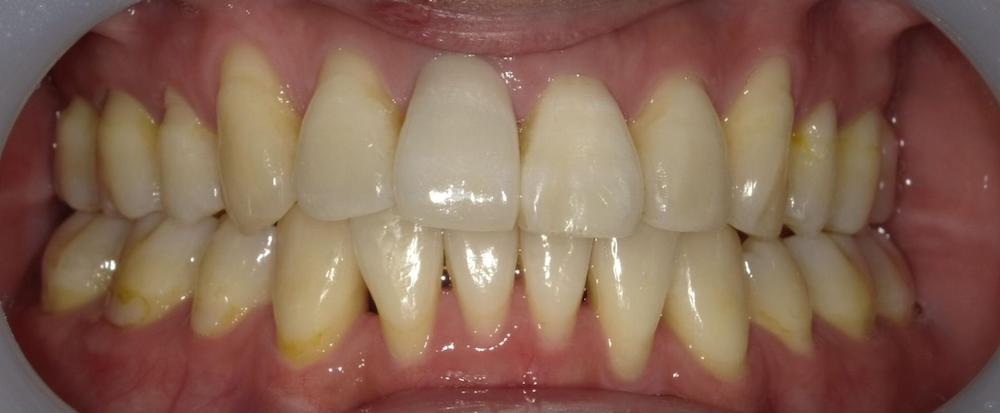

Before

症例2 舌癖による後戻りケース (軽度)

舌を前歯に押し付ける癖があり、徐々に前に出てきてしまったため再矯正を行いました。矯正中から舌トレーニングを行い舌癖の改善に努めました。

- 治療方法 :インビザラインエクスプレス上下

- 治療期間 :6ヶ月

- 治療費用:¥385000(税込)

- 治療のリスク・デメリット :舌癖の改善をする必要がある